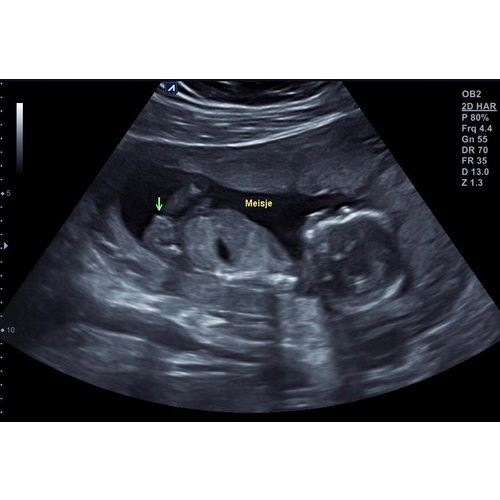

Ik ben bij Pretecho enzo geweest in Vlaardingen. Super aardige echoscopiste, ze nam echt de tijd en had er zelf ook plezier in. Je hebt enorm veel opties en mogelijkheden om uit te kiezen en terwijl ik een 2D echo had geboekt, heeft ze ook nog gratis een stukje 3D echo gemaakt. Ze hebben een mooie kamer met een heel groot scherm waarop je kunt meekijken. De beeldkwaliteit was heel scherp. Ik mocht ook twee mensen meenemen. Je krijgt foto鈥檚 mee na de echo en ook nog eens veel meer foto鈥檚 en filmpjes per e-mail toegestuurd, zo kan je er nog lang van nagenieten. Verderop in de zwangerschap komen we er zeker nog een keer terug voor een 3D echo :-)